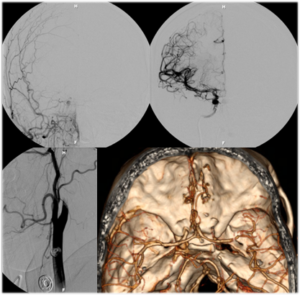

Pipeline Embolization Device Placement for Treatment of Unruptured Aneurysms

Flow diversion is an endovascular technique, used primarily for the treatment of unruptured intracranial aneurysms, whereby a tubular piece of mesh with very small interstices or “flow diverter” is placed inside the parent blood vessel to divert blood flow away from the aneurysm itself.

During a flow-diversion procedure procedure, a microcatheter is navigated beyond the aneurysm without having to enter the aneurysm sac itself. The flow-diverting device is then carefully deployed across the neck of the aneurysm in the parent blood vessel. The only currently approved FDA flow diverting device is the Pipeline™ Embolization Device (PED).